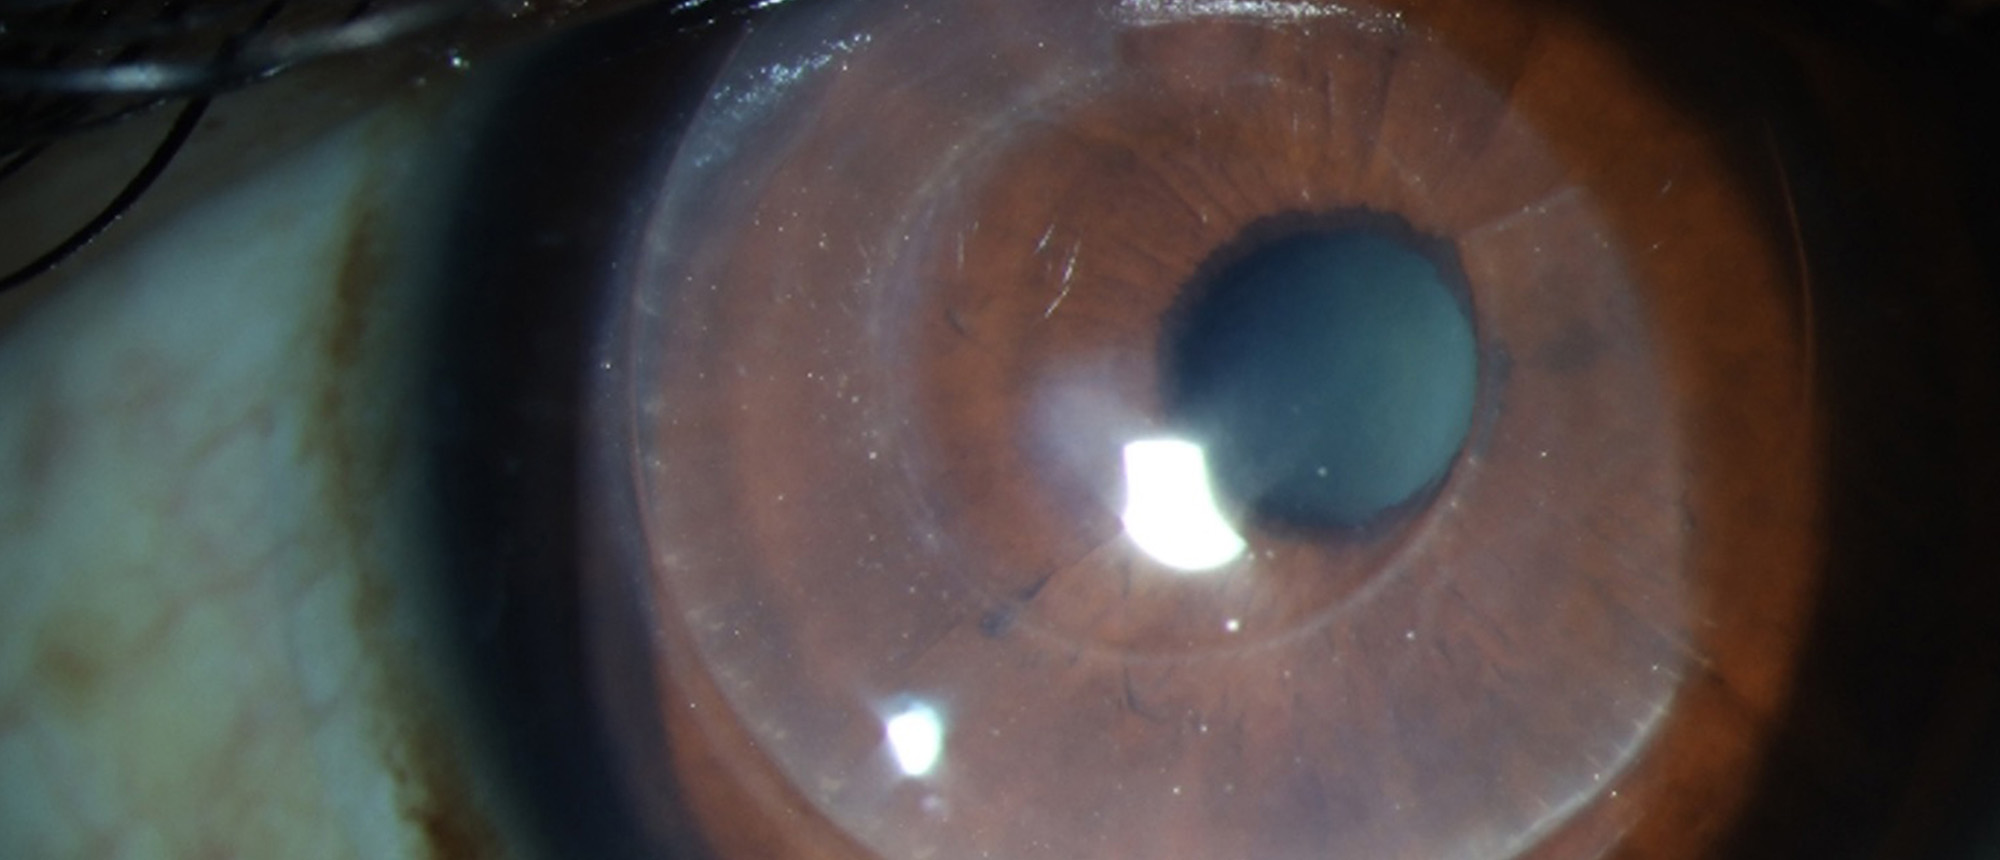

Morgagnian Cataract, Pseudoexfoliation Syndrome, Phacolytic Glaucoma

Specialty: Cataracts and Intraocular Lenses

Type: Ophthalmic Images

Include in Catalogue?: Yes

Original Contributor(s): Jesse D. Sengillo, MD; Jonathan D. Tijerina, MD, MA; Luiz E. Vazquez, MD, PhD

Presenter/Faculty: Sengillo, Tijerina, Vazquez

Slit lamp photos and UBM demonstrating a Morgagnian Cataract in a patient with Pseudoexfoliation Syndrome and Phacolytic Glaucoma.